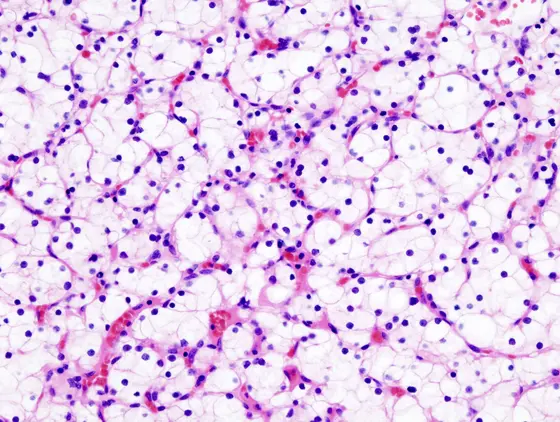

In clear-cell renal cancer, researchers from DKTK Essen found a silent mutation with a major impact on prognosis.

In the tumor genome database “The Cancer Genome Atlas“ (TCGA), the researchers came across the case of a patient with clear-cell renal cancer. A mutation profile was described in the tumor genome that predicted a rather favorable prognosis and a patient survival of 117 months. And yet, this patient had already died 56 months after cancer diagnosis. Upon closer examination, the DKTK researchers found a synonymous mutation in BAP1, a tumor suppressor and an important cancer driver in many tumors.

When a gene is read, only certain regions of the DNA sequence, known as exons, are incorporated into the mature mRNA, which ultimately serves as the building instructions for the protein. The team led by Peña-Llopis has now discovered that the silent BAP1 mutation causes exon no. 11 to be skipped when the individual exons are joined together. This throws the protein blueprint out of sync, resulting in a truncated BAP1 protein that is rapidly degraded. “The complete inactivation of BAP1 as a consequence of this pathogenic synonymous mutation causes higher tumor aggressiveness and decreases almost fourfold the expected patient survival“, says Peña-Llopis, who previously classified this tumor type based solely on inactivating mutations in BAP1 and another tumor suppressor. Peña-Llopis thus recommends paying attention to even the supposedly silent mutations in tumor genome analyses, “especially those used for personalized medicine by providing specific treatments to patients depending on the genomic alterations identified“.